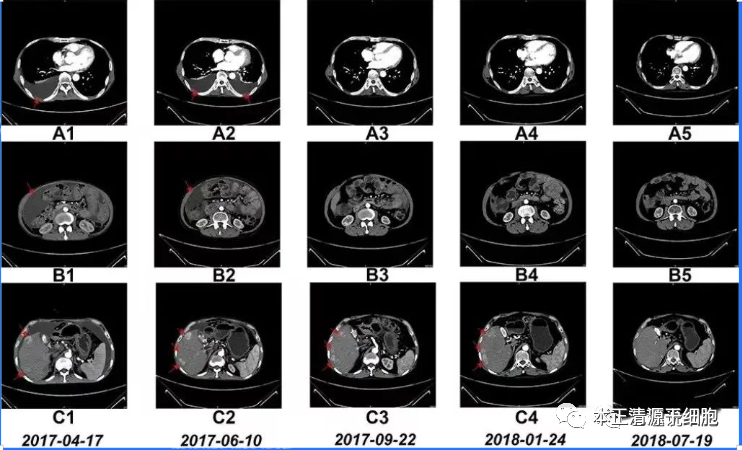

研究人员在NK细胞治疗前后进行了计算机断层扫描 (CT),以进行基于影像学的诊断,并评估临床效率。6个疗程后,患者的胸水和腹水明显减少。自治疗结束以来,患者一直保持这种状态。此外,在NK细胞治疗17个疗程结束后,右肝叶中的多个肿瘤体积减小。

值得一提的是,据后续统计,该名患者的生存时间>48个月,即超过4年!

NK细胞治疗前和治疗期间的CT扫描结果

图A1~A5:CT扫描显示,6个疗程后胸腔积液完全消失;

图B1~B5:CT扫描显示,6个疗程后腹水几乎完全消失;

图C1~C5:CT:扫描显示,肝右叶多个肿瘤的大小在治疗结束后显著缩小;